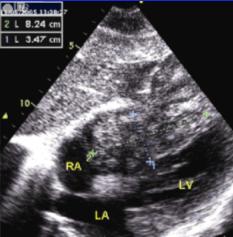

4、15%~30%的患者有心臟受累心臟逐漸增大,出現氣急水腫、進行性頑固性心力衰竭。心律失常較多見,包括陣發性房性心動過速和心房撲動、心房顫動,頻發室性期前收縮亦多見此外各種程度的房室傳導阻滯、低電壓和ST-T改變亦十分常見。累及心臟時,出現心臟擴大心律失常及充血性心力衰竭本病晚期多死於心力衰竭及肝功能衰竭。

血色病性心肌病其它輔助檢查:1、胸部X線有心功不全者常顯示心臟球形增大症狀不明顯者心臟可以正常;2、心電圖可出現各種類型的心律失常有症狀的患者幾乎均有低電壓及ST-T改變;3、肝臟活檢由於肝組織的含鐵量與心肌中的鐵濃度密切相關所以肝臟活檢是診斷心肌鐵質沉著的便利途徑,肝臟鐵含量增加,大於600µg/100mg(乾重);4、心內膜心肌活檢可獲得確診直接證據有報導對本病進行去鐵治療時以心肌活檢含鐵濃度進行監測可避免發生低鐵血症和缺鐵性貧血;5、心內膜心肌活檢是確診RCM的重要手段。根據心內膜心肌病變的不同階段可有壞死血栓形成纖維化三種病理改變。心內膜可附有血栓,血栓內偶有嗜酸性粒細胞;心內膜可呈炎症壞死、肉芽腫、纖維化等多種改變;心肌細胞可發生變性壞死並可伴間質性纖維化改變。有人將心內膜心肌活檢與血流動力學檢查結果相結合,分析RCM的特點及類型,認為舒張末期容積<100ml/m2及左室舒張末期壓力>18mmHg是原發性RCM的突出特點亦有人對符合上述血流動力學標準並接受心內膜活檢的患者進行系統研究,結果提示:①單純限制型者心室重量/容量比為1.2g/ml±0.5g/ml,射血分數58%±5%左心室舒張末期容積67.5ml/m2±12.6ml/m2,左心室舒張末期壓力26.7mmHg±3.5mmHg;②肥厚合併限制型者心室重量/容積比1.5g/ml±0.07g/ml,射血分數62%±1%左心室舒張末期容積69ml/m2±10ml/m2,左心室舒張末期壓力30mmHg±7mmHg;③輕度擴張限制型者心室重量/容積比為0.9g/ml左心室舒張末期容積為98ml/m2,而左心室舒張末期壓力為40mmHg。組織學及電鏡觀察發現各型均存在心肌和肌原纖維排列紊亂及心內膜心肌間質纖維化;6、CT和磁共振是鑑別RCM和縮窄性心包炎最準確的無創傷性檢查手段RCM者心包不增厚心包厚度≤4mm時可排除縮窄性心包炎;而心包增厚支持縮窄性心包炎的診斷;7、放射性核素心室造影右心型RCM造影的特點為:①右心房明顯擴大伴核素滯留;②右室向左移位其心尖部顯示不清左心室位於右心室的左後方右心室流出道增寬右心室位相延遲,右心功能降低;③肺部顯像較差肺部核素通過時間延遲;④左心室位相及功能一般在正常範圍。